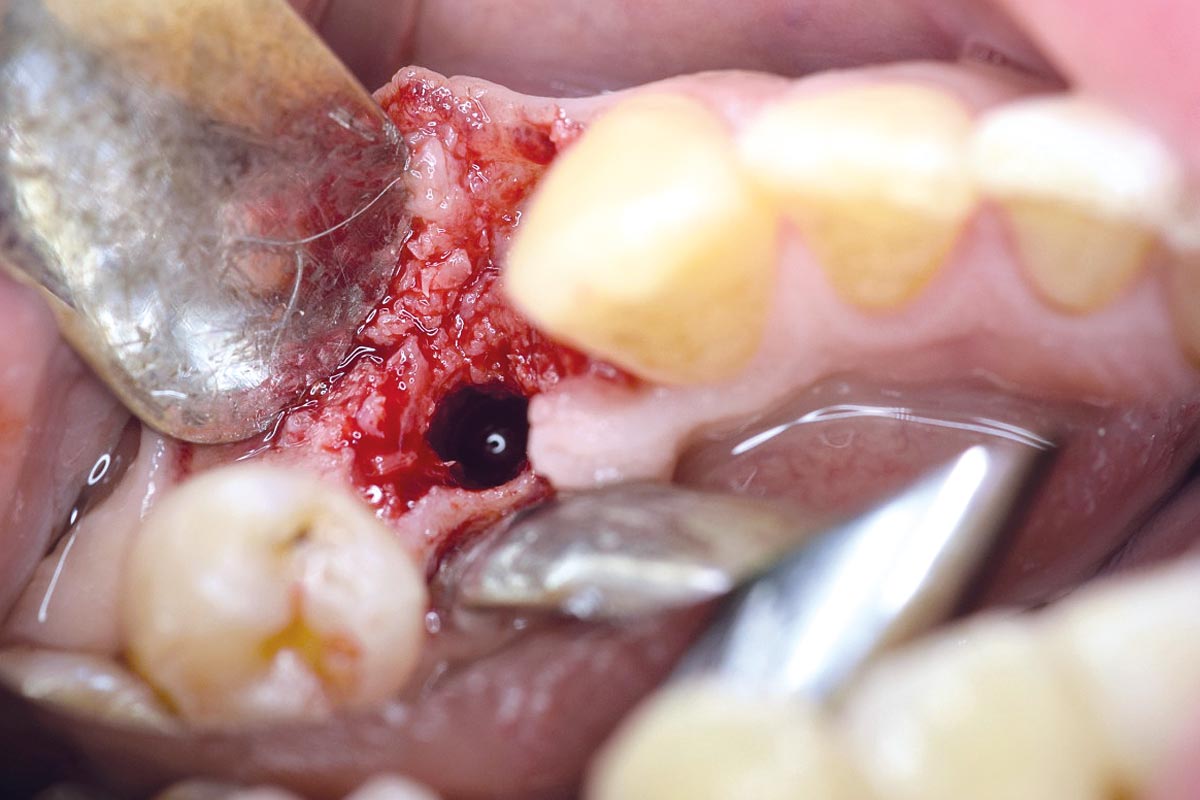

Posterior socket preservation using maxgraft® and permamem® - Dr. C. Landsberg

Initial clinical situation: 9 mm pocket depth associated with root fracture